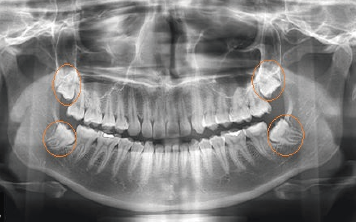

Es la rama de la odontología encargada del diagnóstico y tratamiento quirúrgico de las alteraciones en los tejidos duros y blandos de la boca como patologías infecciosas, tumorales y de malformaciones bucales y maxilofaciales, utilizando como ayudas diagnósticas la imagenología, la histopatología y pruebas de laboratorio clínico.

El odontólogo especialista en esta área posee el conocimiento y la destreza para toma de biopsias, realización de tratamientos de urgencias, manejo de alteraciones de la boca como: frenillos traccionantes, dientes retenidos o incluidos, cirugías pre protésicas, cirugías maxilo facilaes y reconstructivas.